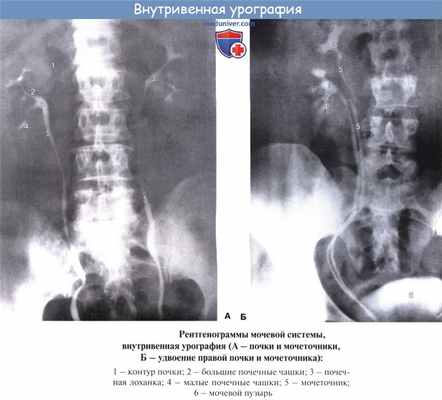

Рентгеновские лучи позволяют исследовать у живого экскреторное дерево почки: чашки, лоханку, мочеточник. Для этого инъецируют в кровь контрастное вещество, которое выделяется через почки и, присоединяясь к моче, дает на рентгенограмме силуэт почечной лоханки и мочеточника (контрастное вещество можно ввести и непосредственно в почечную лоханку с помощью мочеточникового катетера и особого инструмента — цистоскопа). Этот метод называется уретеропиелография.

Лоханка на рентгенограмме проецируется на уровне между I и II поясничными позвонками, причем справа несколько ниже, чем слева.

По отношению к почечной паренхиме отмечают два типа расположения почечной лоханки: экстраренальный, когда часть ее находится вне почки, и интраренальный, когда лоханка не выходит за пределы почечной пазухи.

Рентгенологическое исследование выявляет перистальтику почечной лоханки. При помощи серийных рентгенограмм можно видеть, как сокращаются и расслабляются отдельные чашки и лоханка, как открывается и за крывается верхний сфинктер мочеточника. Эти функциональные изменения имеют ритмичный характер, поэтому различаются систола и диастола экскреторного дерева почки. Процесс опорожнения экскреторного дерева протекает так, что большие чашки сокращаются (систола), а лоханка расслабляется (диастола) и наоборот. Полное опорожнение происходит в течение 6 — 8 мин.

Почки располагаются по обеим сторонам позвоночника, обычно на уровне ThXII-LIII (справа) и ThXI—LII (слева). В отличие от взрослых у детей, особенно младшего возраста, почки относительно большие, поэтому на рентгенограммах нижние полюса их расположены ближе к гребню подвздошной кости и нередко находятся на уровне последнего. Продольная ось почки расположена параллельно краю поясничной мышцы, так что угол, образованный продольными осями обеих почек, открыт книзу и равен 20—30°, причем у мужчин он обычно несколько больше. Знание этого признака, который легко определяется на рентгенограмме, очень важно, поскольку при патологических состояниях (аномалии развития, пиелонефрит, нефроптоз, паранефрит и т.д.) направление продольной оси почки может меняться с одной или двух сторон.

Нормальные почки дают на рентгенограмме гомогенные бобовидные тени с ровными контурами размером 12x7 см (у мужчин несколько больше, у женщин несколько меньше). Правая почка располагается на 1,5—2 см ниже левой, и тень ее пересекается ХII ребром обычно посредине. У 30% людей обе почки расположены на одинаковом уровне, у 5% людей левая почка расположена ниже правой.

Мочеточники на всем протяжении имеют четыре физиологических сужения:

1) в месте перехода лоханки в мочеточник;

2) над подвздошными сосудами;

3) в предпузырном отделе (юкставезикальная часть мочеточника);

4) в интрамуральном отделе.

Мочеточник состоит из трех цистоидов — веретенообразных резервуаров, между которыми на уретерограмме обычно заметны сужения. Длина мочеточника взрослого человека составляет 25—30 см, наружный диаметр — 1—1,3 см, внутренний диаметр — 0,4—0,6 см.

В мочевом пузыре различают верхушку, шейку, дно и тело. Верхушка - место перехода мочевого пузыря в среднюю пузырно-пупочную связку (заросший урахус). Дно — наиболее широкая нижнезадняя часть мочевого пузыря, обращенная у мужчин в сторону прямой кишки, у женщин — в сторону матки и верхней части передней стенки влагалища. Шейка - суженная часть мочевого пузыря, граничащая с мочеиспускательным каналом. Средний отдел, расположенный между верхушкой и дном мочевого пузыря, называется телом.

В наполненном мочевом пузыре различают переднюю, заднюю, верхнюю, правую и левую боковые стенки. На рентгенограммах нормальный мочевой пузырь, наполненный рентгеноконтрастным веществом, имеет овальную (у женщин) или шаровидную (у мужчин) форму и ровные четкие контуры. Нижняя граница мочевого пузыря обычно расположена на уровне верхнего края симфиза лобковых костей или немного ниже.